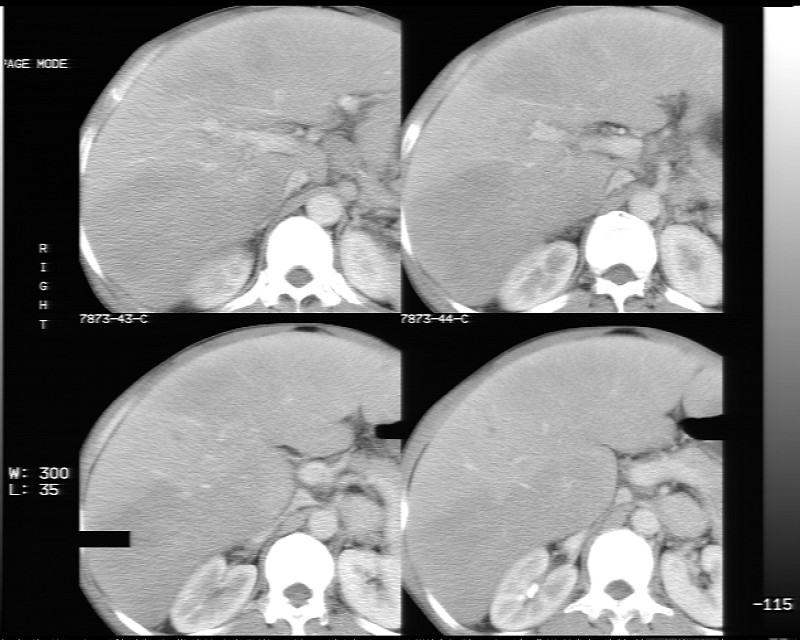

动态增强示:

支持脂肪肝【无占位性,高低密度区同期强化,平扫与强化的密度成比例】

1、不均匀脂肪肝;2、布加氏综合症(肝脏肿大,门脉纤细,下腔海绵状变性,肠系膜上静脉显著扩张)。